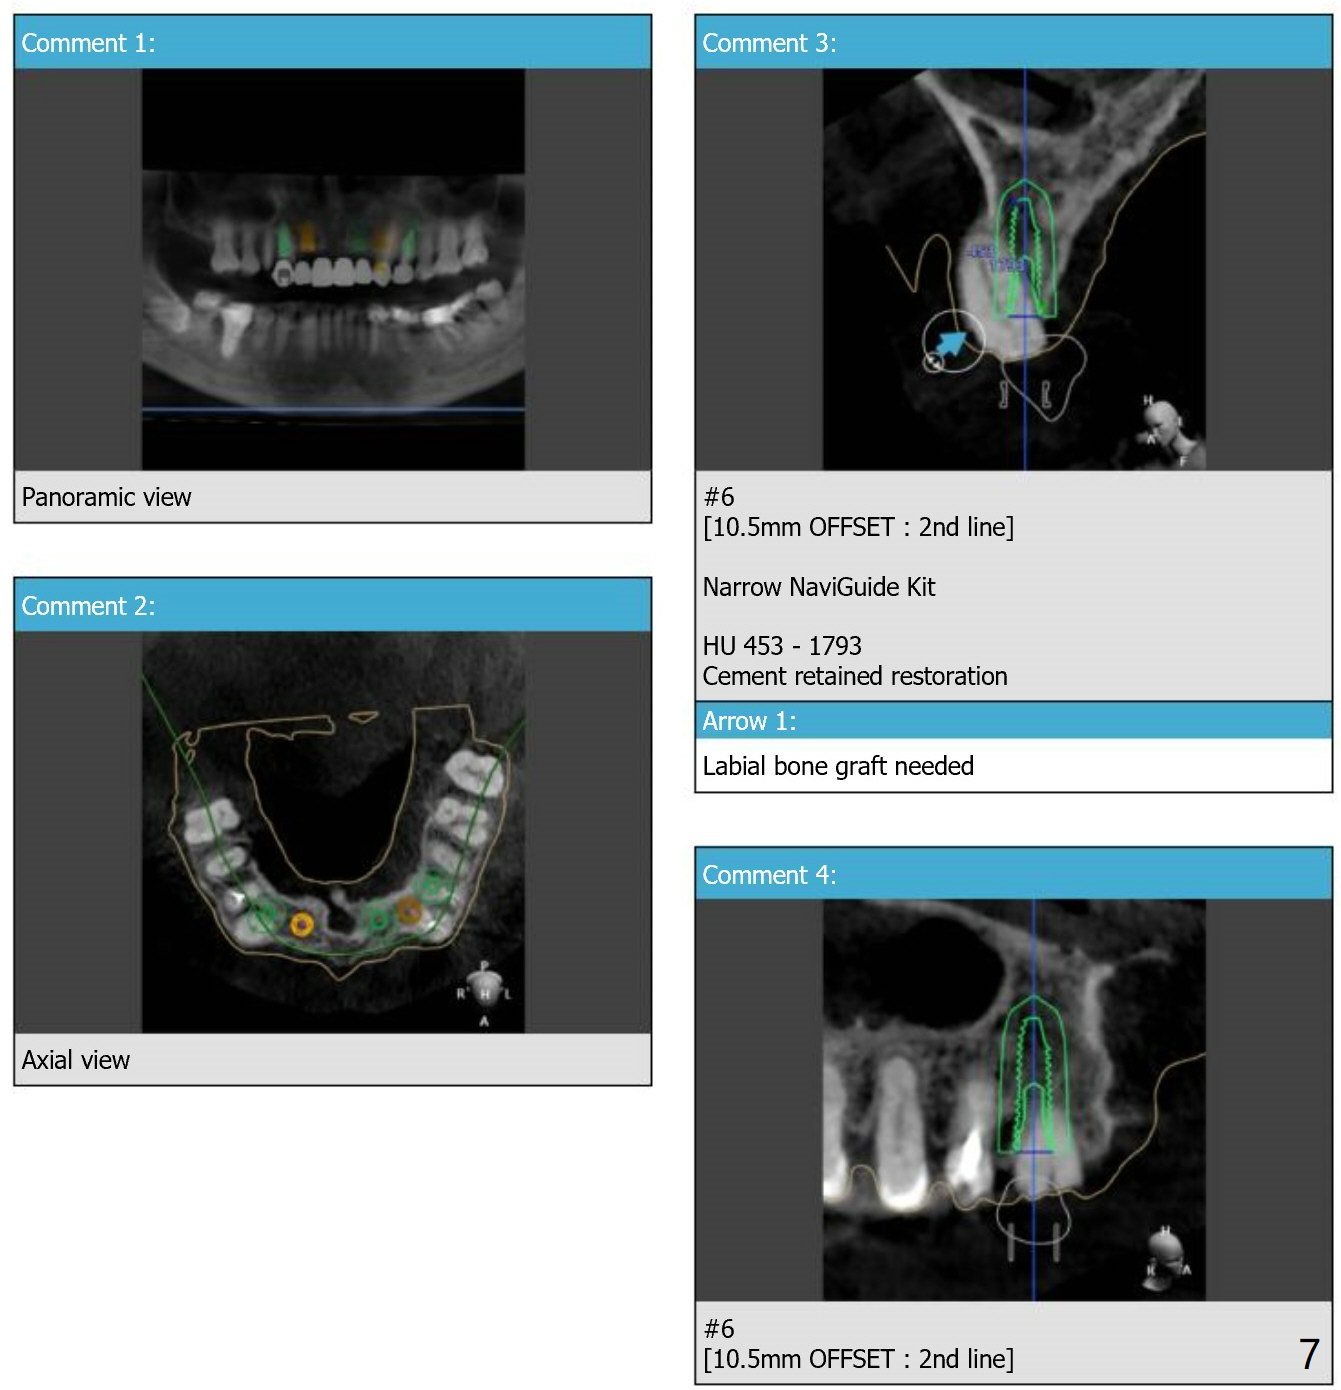

Since the apex of the tooth #5 seems to tilt mesial, implants at #6 and 7 will be placed mesial intentionally with diameters of 3.5 and 3 mm (Fig.1-3). On the left side with minor space issue, two-piece implants with 3.5 mm in diameter will be placed at #11-12 (Fig.5-6). After implant osteointegration, a 4-unit FPD will be fabricated between #7-10. Return to Upper Arch Immediate Implant, Trajectory, Metronidazole Xin Wei, DDS, PhD, MS 1st edition 11/09/2018, last revision 11/16/2018